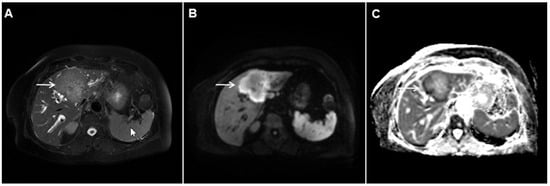

Hydatid liver disease results from incidental infection with Echinococcus granulosus, which causes cystic echinococcosis, or Echinococcus multilocularis, which causes alveolar echinococcosis (AE) [60]. If characteristic imaging features are present in the form of a cystic lesion with multiple internal daughter cysts and the absence of postcontrast enhancement, there are no difficulties in establishing the correct diagnosis [61]. However, in cases of inactive infection with solid-appearing pseudotumors making the correct diagnosis might be difficult, and in certain cases mICC may be suspected [62]. Although the absence of postcontrast enhancement is a typical finding in solid-appearing liver echinococcosis, a mild delayed peripheral opacification corresponding to the fibroinflammatory rim may be present [62]. In such cases, the visualization of dystrophic calcifications is helpful to distinguish between hydatid disease and mICC (Figure 14) [62]. Since the detection of calcifications is difficult via MRI examinations, in doubtful cases an additional CT examination should be performed.

Figure 14.

Solid-appearing liver echinococcosis in a 54-year-old woman. An axial T2-weighted FS image (A) shows a heterogeneous liver lesion (arrow) in liver segment II with internal hypointense areas. A slight biliary dilatation adjacent to the lesion can also be seen. The lesion (arrow) is hypointense in the arterial phase (B) and remains hypointense in the portal venous phase (C), simulating a hypovascular liver tumor. Hematoxylin and eosin (H&E) staining (D) showed an echinococcal cyst with germinative membranes (arrow) and the thick hyalinized wall of the cyst (dashed arrow) surrounded by normal liver parenchyma (arrowhead); original magnification ×40.

While the diagnosis of a typical hepatic hydatid cyst is in most cases straightforward, the alveolar form of hydatid disease frequently represents a diagnostic challenge [63,64]. According to Kodama et al., AE may present in one of five distinct ways in an MRI scan [65]. Among them, type 2 with multiple small round cysts and a solid component, type 3 with a solid component containing multiple small cysts surrounding a large, irregular pseudocyst, and type 4 presenting as a heterogeneous infiltrative mass with irregular borders might be confused with hepatic malignant tumors, especially mICC [65]. In this regard, the presence of an irregular, infiltrative hypovascular lesion with mild peripheral enhancement in the delayed phase may be easily misinterpreted as mICC (Figure 15) [62,63,66]. Additionally, if large areas of necrosis in hepatic alveolar echinococcosis are present, necrotic mICC may be suspected [64,66]. Furthermore, ancillary imaging features that are considered characteristic of mICC, such as the invasion of the portal vein leading to lobar atrophy, biliary dilatation, and capsular retraction, may also be detected in hepatic AE [67]. Concerning the differential diagnosis between these entities, Mueller et al. found that no or septal enhancement in an MRI scan and matrix calcifications seen in a CT scan are the strongest indicators of AE [66]. Moreover, in the context of rim enhancement, which may be present in AE—leading to confusion with mICC—Wa et al. found that rim enhancement of mICC was more irregular and thicker than the linear rim of AE lesions [63]. To prevent potential misdiagnosis, in all cases when AE is suspected CT should be performed in addition to MRI, as it provides for the detection of typical calcifications and the absence of distinct vasculature inside the mass [61,64,65].

Figure 15.

Alveolar echinoccosis in a 31-year-old man. An irregularly shaped lesion (arrow) is seen in liver segment VI, presenting as heterogeneously slightly hyperintense in the axial T2-weighted image (A) and hypointense in the plain T1-weighted image (B). Note the perilesional biliary dilatation. No enhancement is detected in the central part of the lesion (arrow), while there is subtle enhancement in the posteromedial part of the lesion in the arterial (C) and portal venous phases (D). The lesion does not show restricted diffusion (E). Hematoxylin and eosin (H&E) staining showed alveolar echinococcosis with multiple multilocular cysts (arrows) and hydatid membranes (dashed arrows) (F); original magnification ×40.